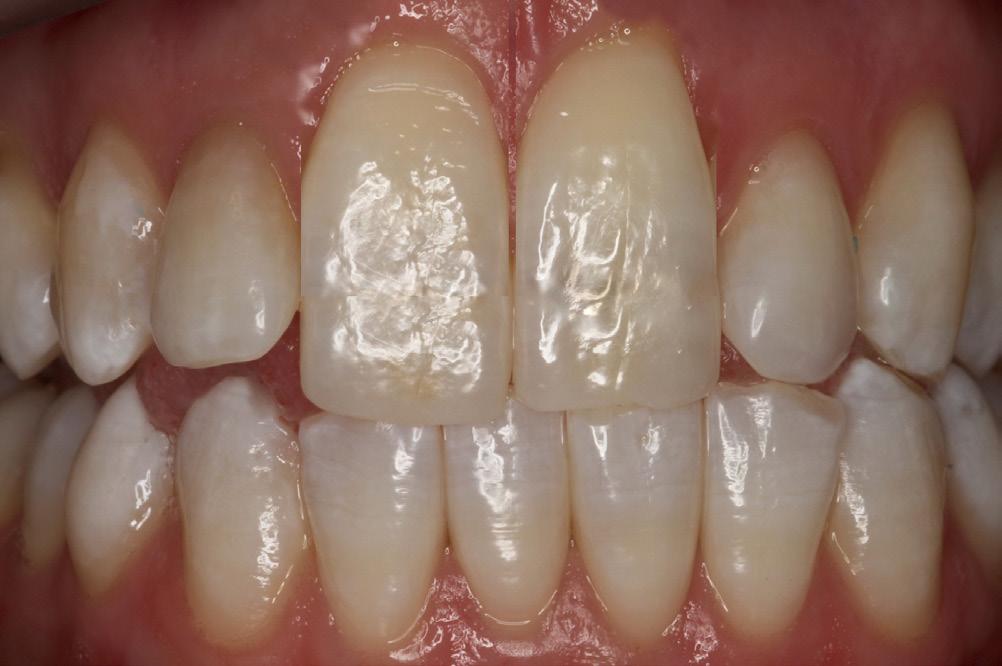

A substantial increase in the apparent length of a tooth, specifically in the anterior labial region, detracts from the esthetic smile. When restoring a Class V decay or abfraction, or perhaps a small gingival recession, an enamel-colored resin is commonly placed at the labial DEJ. Increasing the maxillary central incisor’s vertical aspect (Fig. 1) by a mere 3mm adds 30% to the apparent vertical dimension, significantly altering the cervico-incisal to

mesio-distal (CI:MD) ratio, totally upsetting the esthetic parameters of the smile. (Fig. 2) In situations where there is moderate recession, the visual imbalance is even further impaired. The CI:MD ratio impact is even greater on maxillary laterals and mandibular incisors (average 9.0mm CI). Maxillary and mandibular cuspids (average 10-11mm CI) are often the teeth most affected by gingival recession, and are also highly visible both anteriorly and laterally.

1: Normal length maxillary central incisors – expected appearance

Figure 2: Maxillary incisors apparent length increased by 30%very unnatural and unesthetic